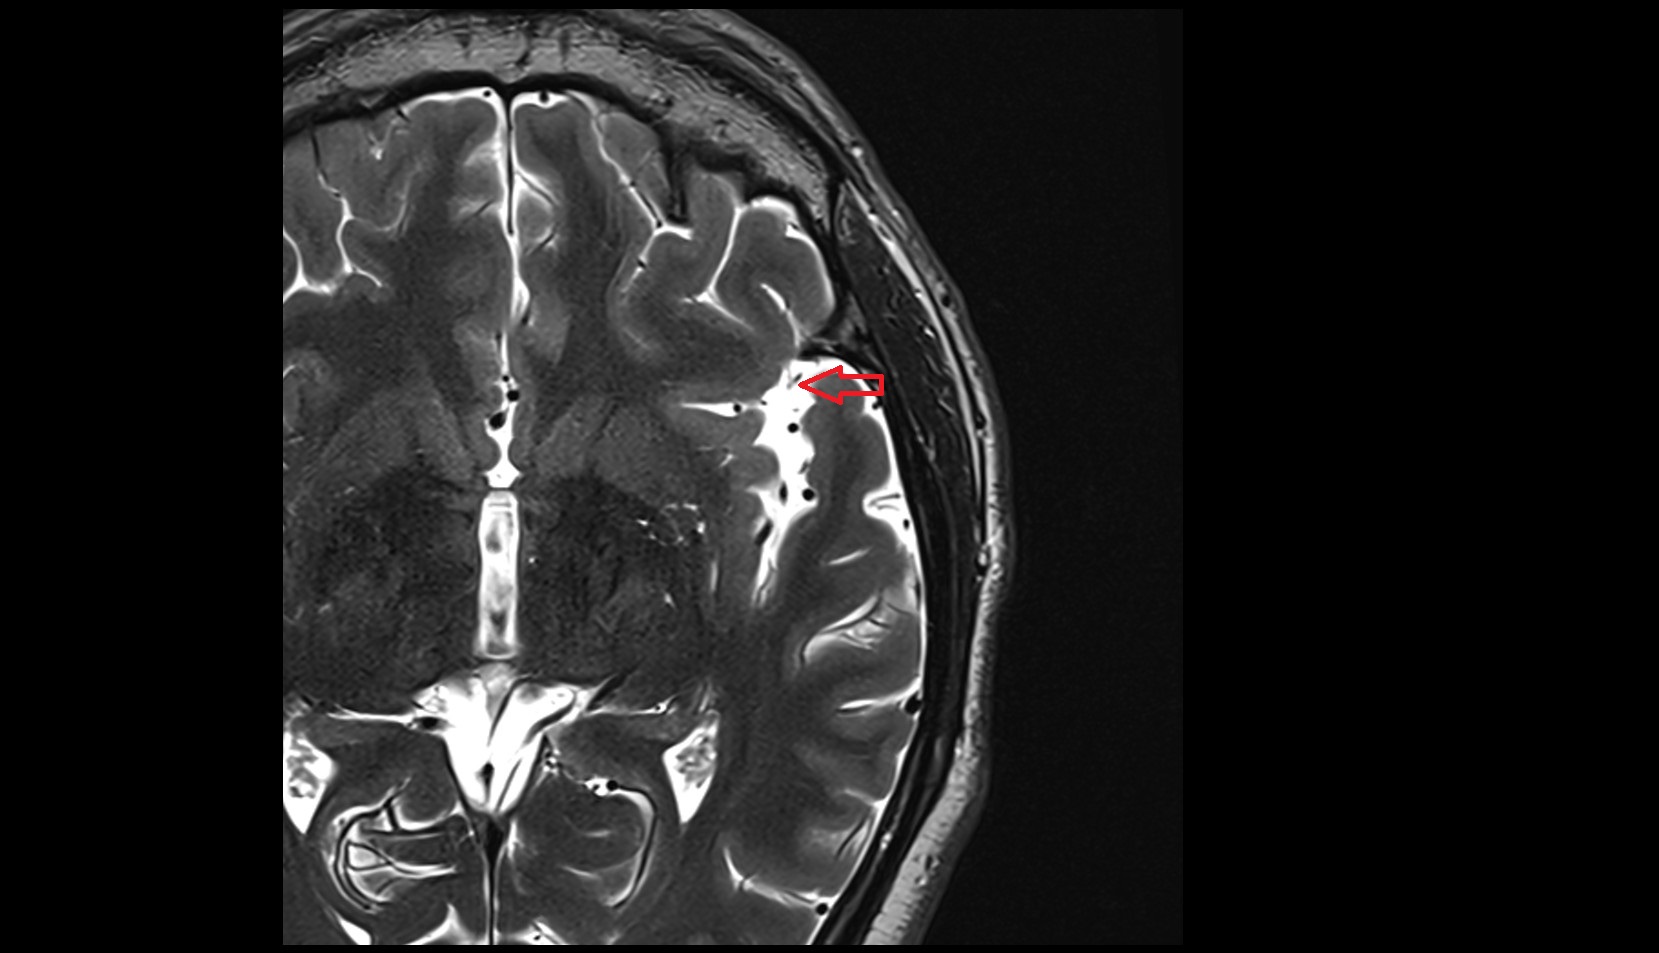

- Body of hippocampus

- Head of hippocampus

- Tail of hippocampus

- Hippocampus